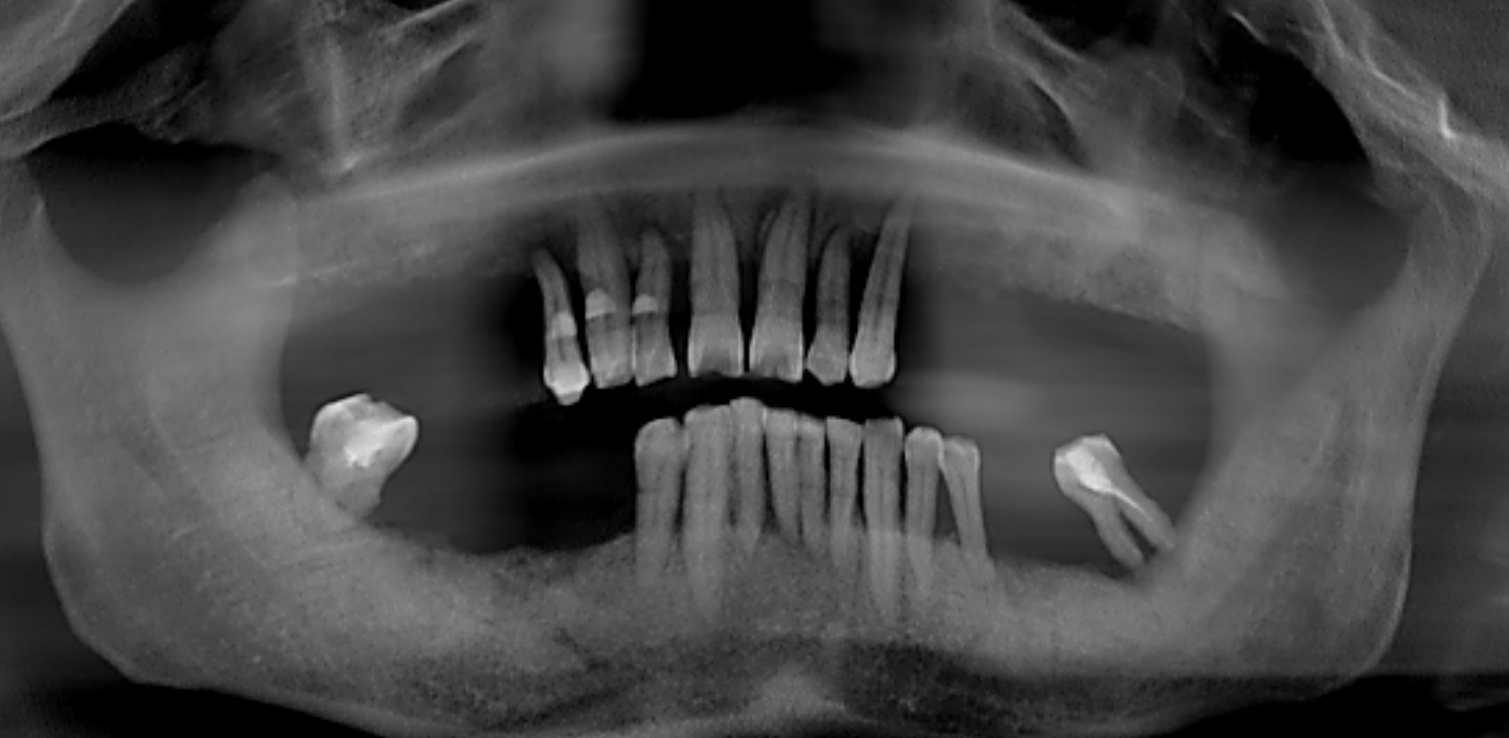

X线检查:上颌余留牙牙槽骨吸收至根尖1/3,预留骨量尚可,骨密度II-III类。

CT检查:后牙余留骨量高度10-12mm,前牙骨高度12-14mm,宽度均大于6mm。